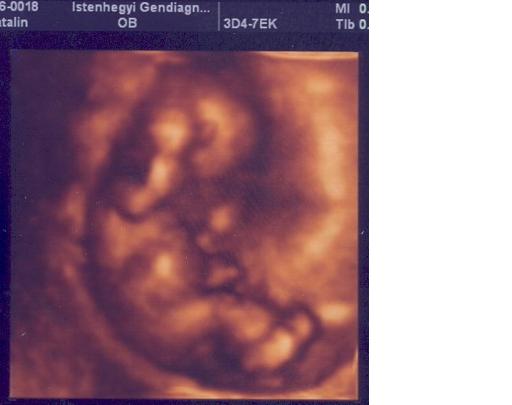

És a babód csudaszép formás kis lurkó! Büszke lehetsz rá